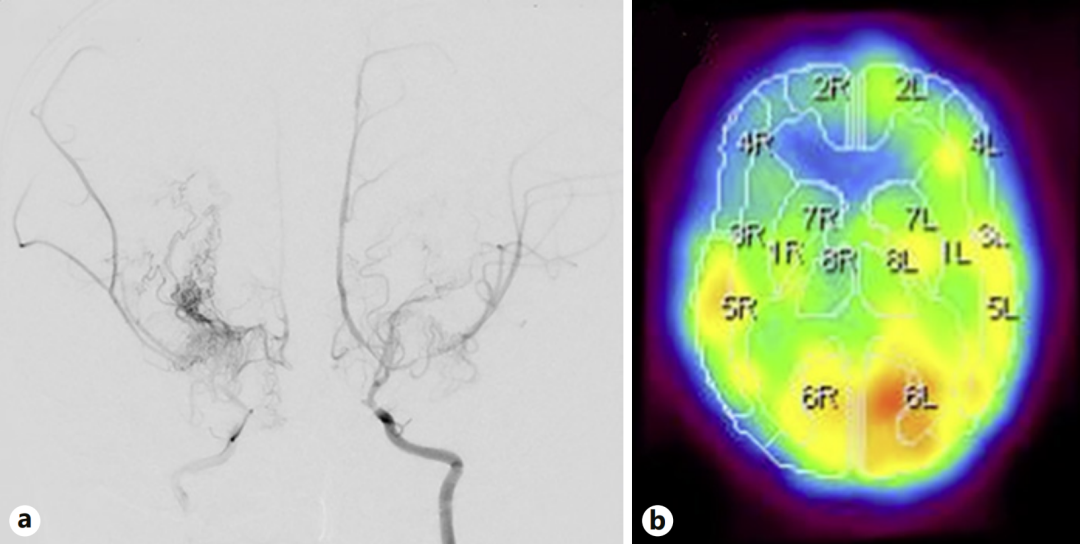

- 数字减影血管造影(DSA)显示双侧颈内动脉末端、大脑前动脉近端及大脑中动脉严重狭窄。(如图a,就像三条主干道同时堵车,脑组织正在 “缺氧” 的边缘挣扎。)

- 123I-IMP SPECT显示右侧额叶的脑血流已经显著减少,正是这里发生过脑梗死(如图b,这解释了她反复猝倒的原因:大脑缺血时,身体会突然失去力量。)